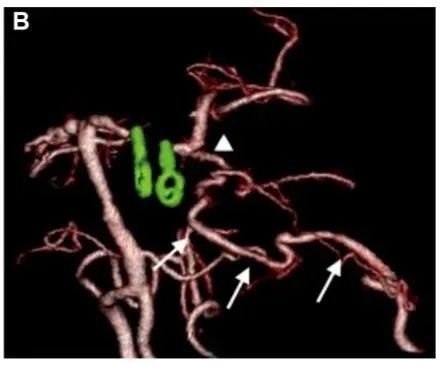

术前 3D-DSA 显示位于左侧 P1-P2 交界处动脉瘤。

术后3D CTA显示左侧 PCA 区血管穿支(箭头)和重建的PTA血管(箭头)的血流通畅。

术后1年血管造影:显示已排除动脉瘤且左侧 PCA 循环通畅。